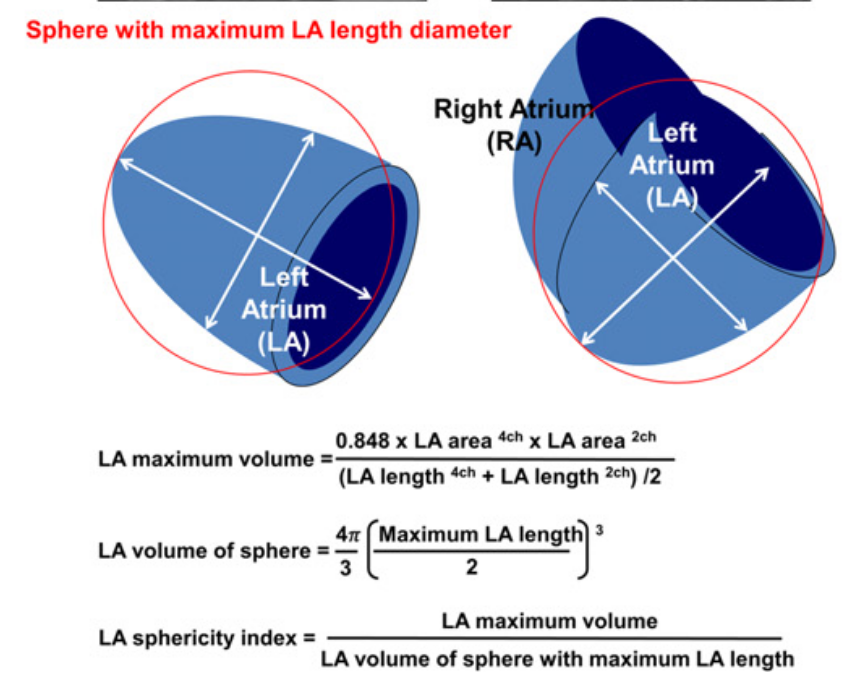

Sphericity index was calculated as the ratio of LA maximum volume to the volume of a sphere with maximum LA length diameter among atrial length and transverse length